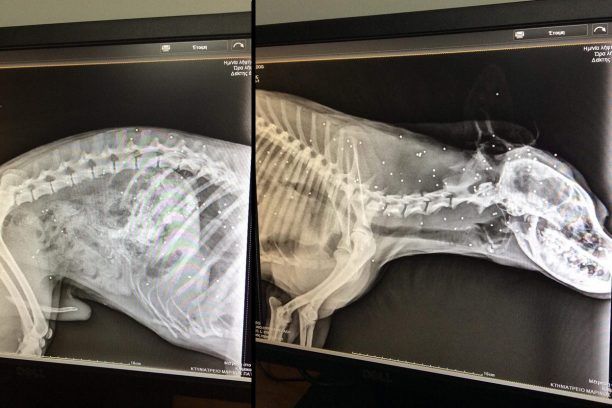

Στις 29 Ιανουαρίου ένας κυνηγός συνελήφθη στο πλαίσιο της αυτόφωρης διαδικασίας καθώς πυροβόλησε και σκότωσε (το ζώο τελικά πέθανε στις 30 Ιανουαρίου) στην περιοχή Κοιλιωμένο Ζακύνθου έναν αδέσποτο σκύλο. Το σκυλί μεταφέρθηκε στο κτηνιατρείο του Μαρίνου Πατίρη όπου και κατέληξε. Στις φωτογραφίες τις οποίες έστειλε στο www.zoosos.gr η Δήμητρα Κοντονή εκ μέρους του σωματείου «Zante Strays» βλέπετε τα δεκάδες σκάγια στο σώμα του ζώου…